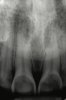

Another intrinsic factor is the patient's gastric acid entering the oral cavity. The source of intrinsic stomach acid may range from rumination or gastroesophageal reflux to chronic alcoholism, pregnancy, or vomiting caused by anorexia nervosa or bulimia nervosa.13 Figure 1 through Figure 3 show the radiographic presentation and clinical examples of dental erosion in advanced stages in the same patient caused by the combination of bulimia nervosa and chronic alcoholism.

Fig 2. Facial erosion of maxillary (Fig 2) and mandibular (Fig 3) anterior teeth.

Figure 2